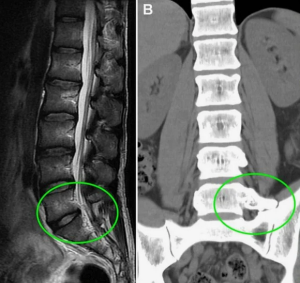

Заключение мультиспиральной компьютерной томографии (МСКТ): «Дегенеративные изменения поясничного отдела позвоночника. Узел Шморля тел LV и SI позвонков. Остеохондроз 2-3-го периода. Умеренное сужение межпозвонкового отверстия Ly-Sr Сакрализация LV справа» (рис. 1).

По данным магнитно-резонансной томографии (МРТ) поясничного отдела позвоночника сдавления спинномозговых корешков не выявлено (рис. 2).